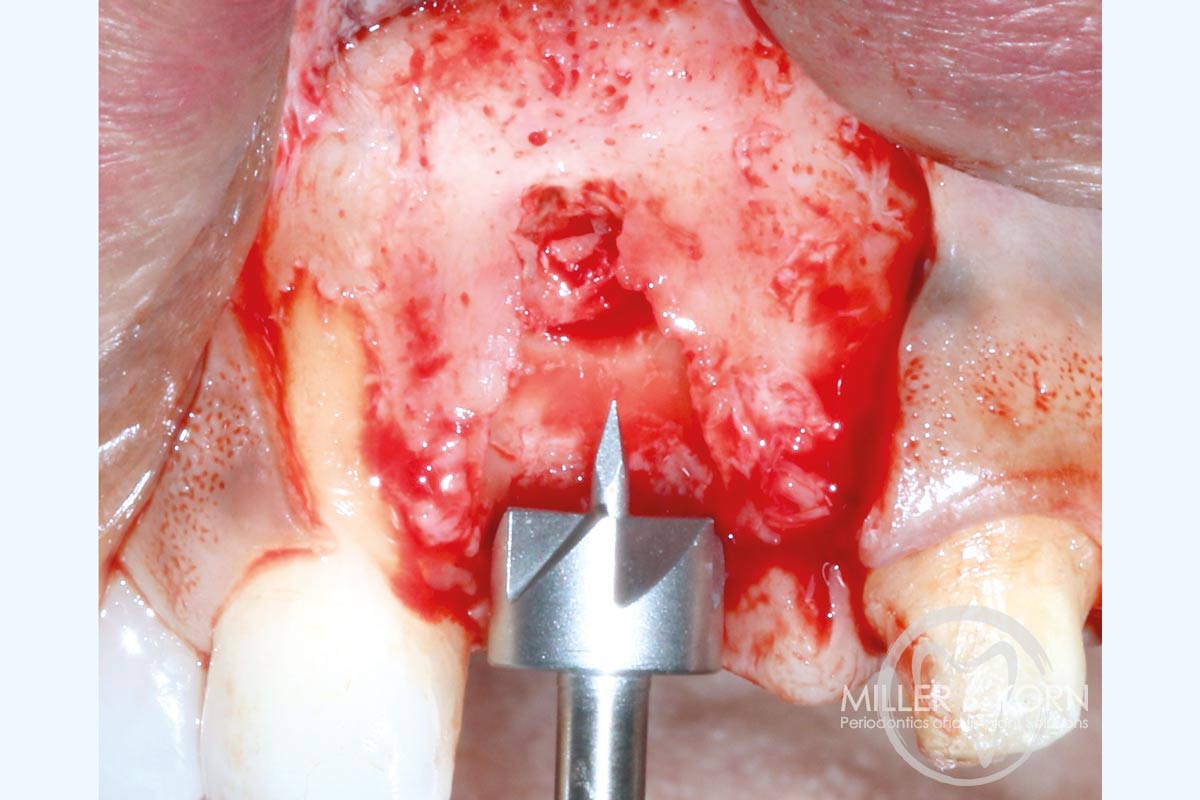

6/22 - Trephine drilling to prepare the site for the allograft ring.Immediate implant placement and regeneration of ridge using an allograft bone ring and Jason® membrane - Drs. Miller and Korn

7/22 - Collecting autogenous bone chips.Immediate implant placement and regeneration of ridge using an allograft bone ring and Jason® membrane - Drs. Miller and Korn

8/22 - Use of the planator to create a uniform ring bed.Immediate implant placement and regeneration of ridge using an allograft bone ring and Jason® membrane - Drs. Miller and Korn